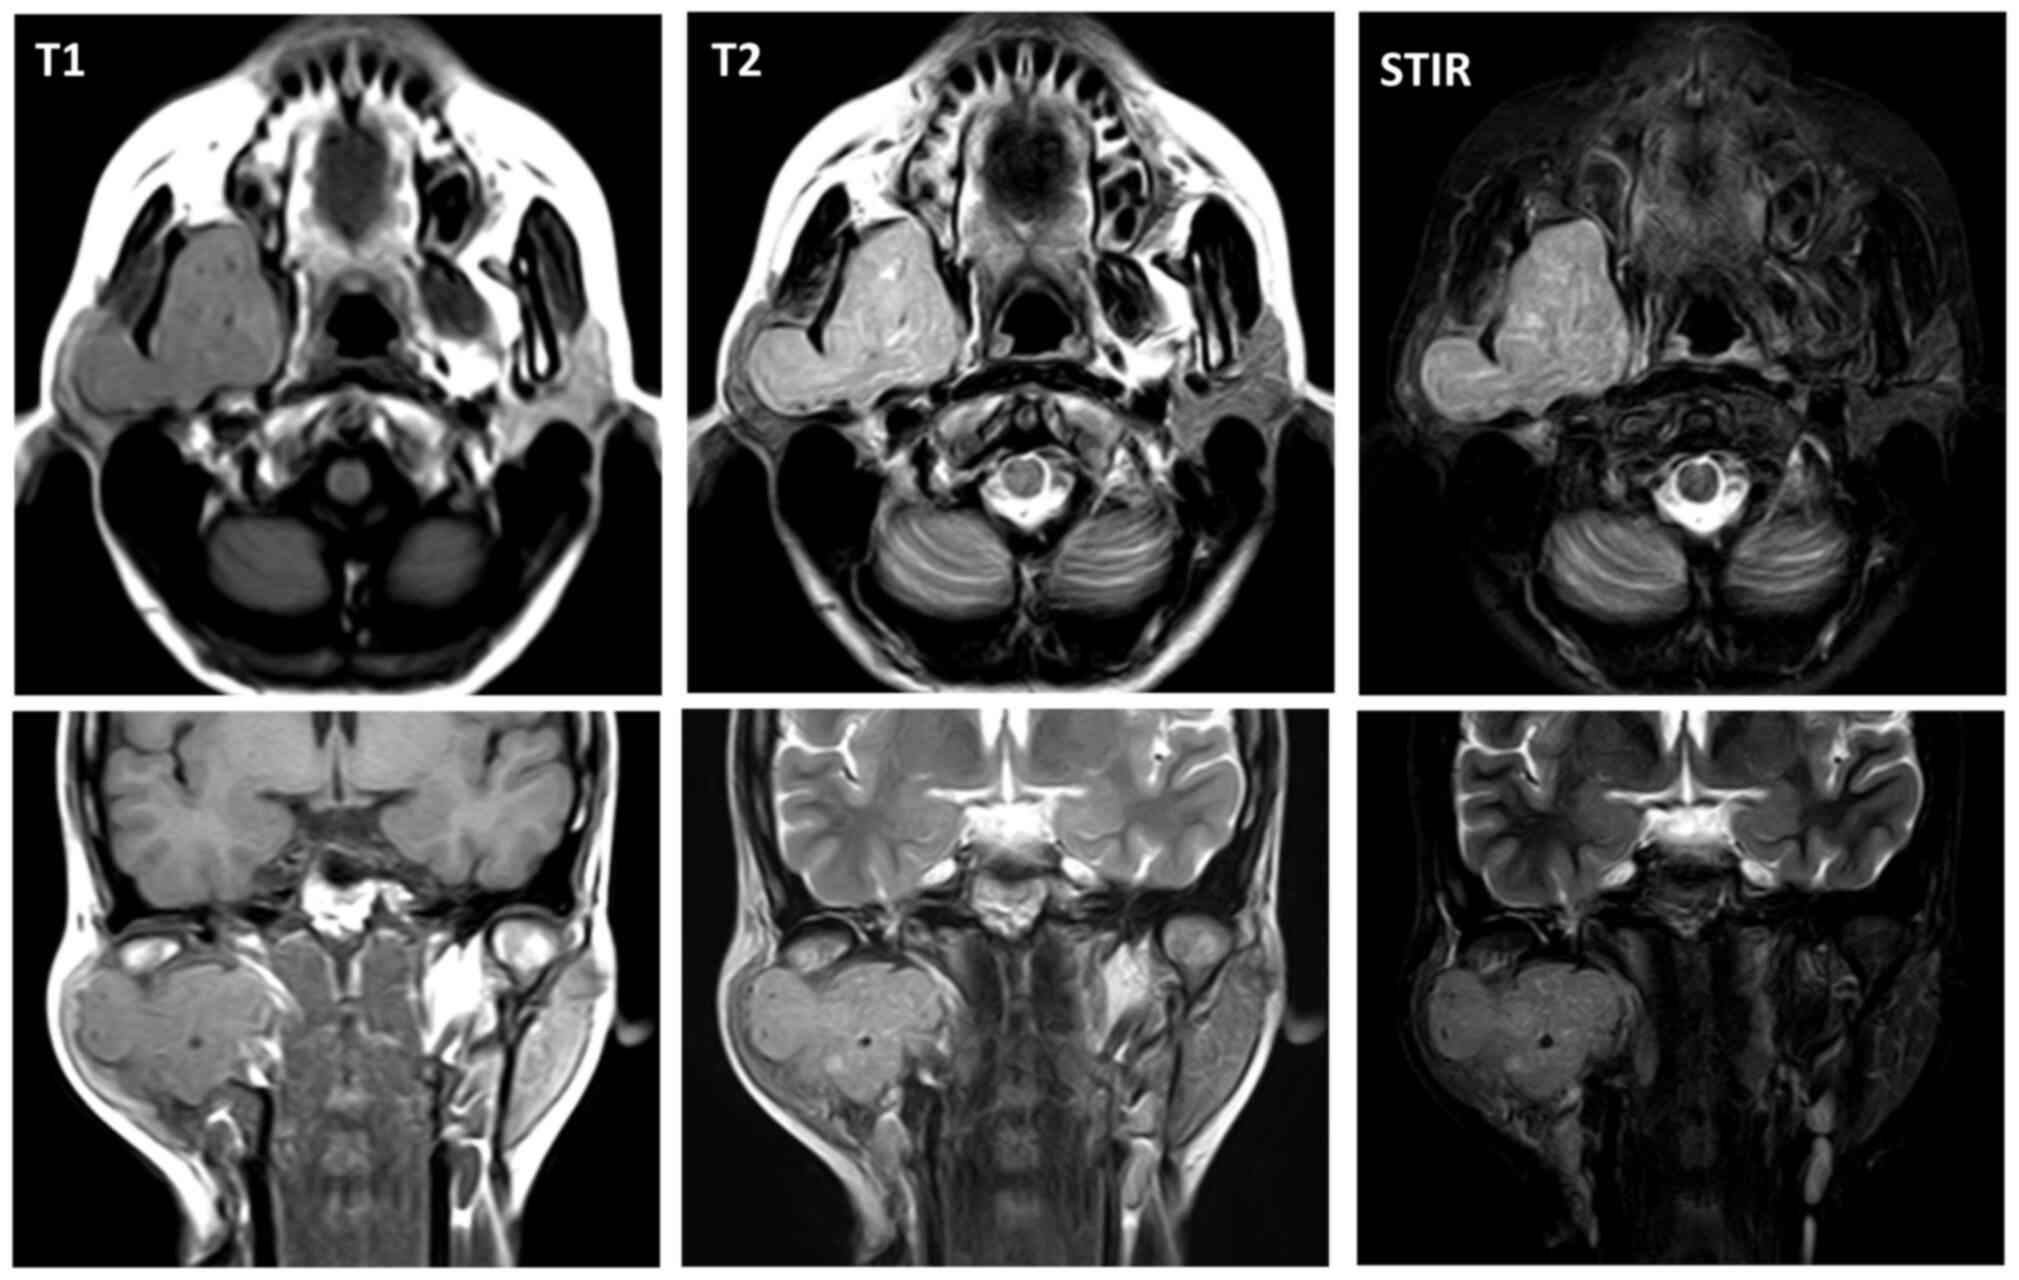

Successful shrinkage of the tumor was seen in MRI 3 years after treatment without recurrence (Fig. 6). Slight numbness of the lower lip, trismus, occasional light dizziness and sustained tinnitus remained as problematic disorders.

Figure 6.

Magnetic resonance imaging (MRI) three years after treatment.